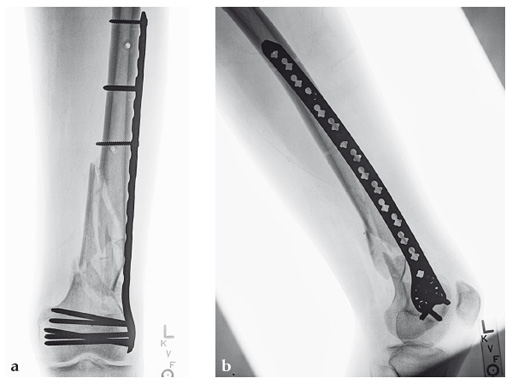

Case 2: A 69-year-old man following revision total knee arthroplasty with a megaprosthesis, requiring an osteotomy of his femoral shaft for realignment of his femoral component. The patient developed a nonunion of his osteotomy and subsequently fractured the stem of his megaprosthesis.

Surgical treatment of this nonunion consisted of compression plating using the VA-LCP Curved Condylar Plate. The arthroplasty components were stable. The proximal piece of the stem was extremely well fixed. Variable-angle locked screws were targeted between his femoral shell and stem in the distal segment allowing excellent distal fixation such that an articulated tensioning device could be attached proximally and the nonunion could be compressed and the alignment improved.